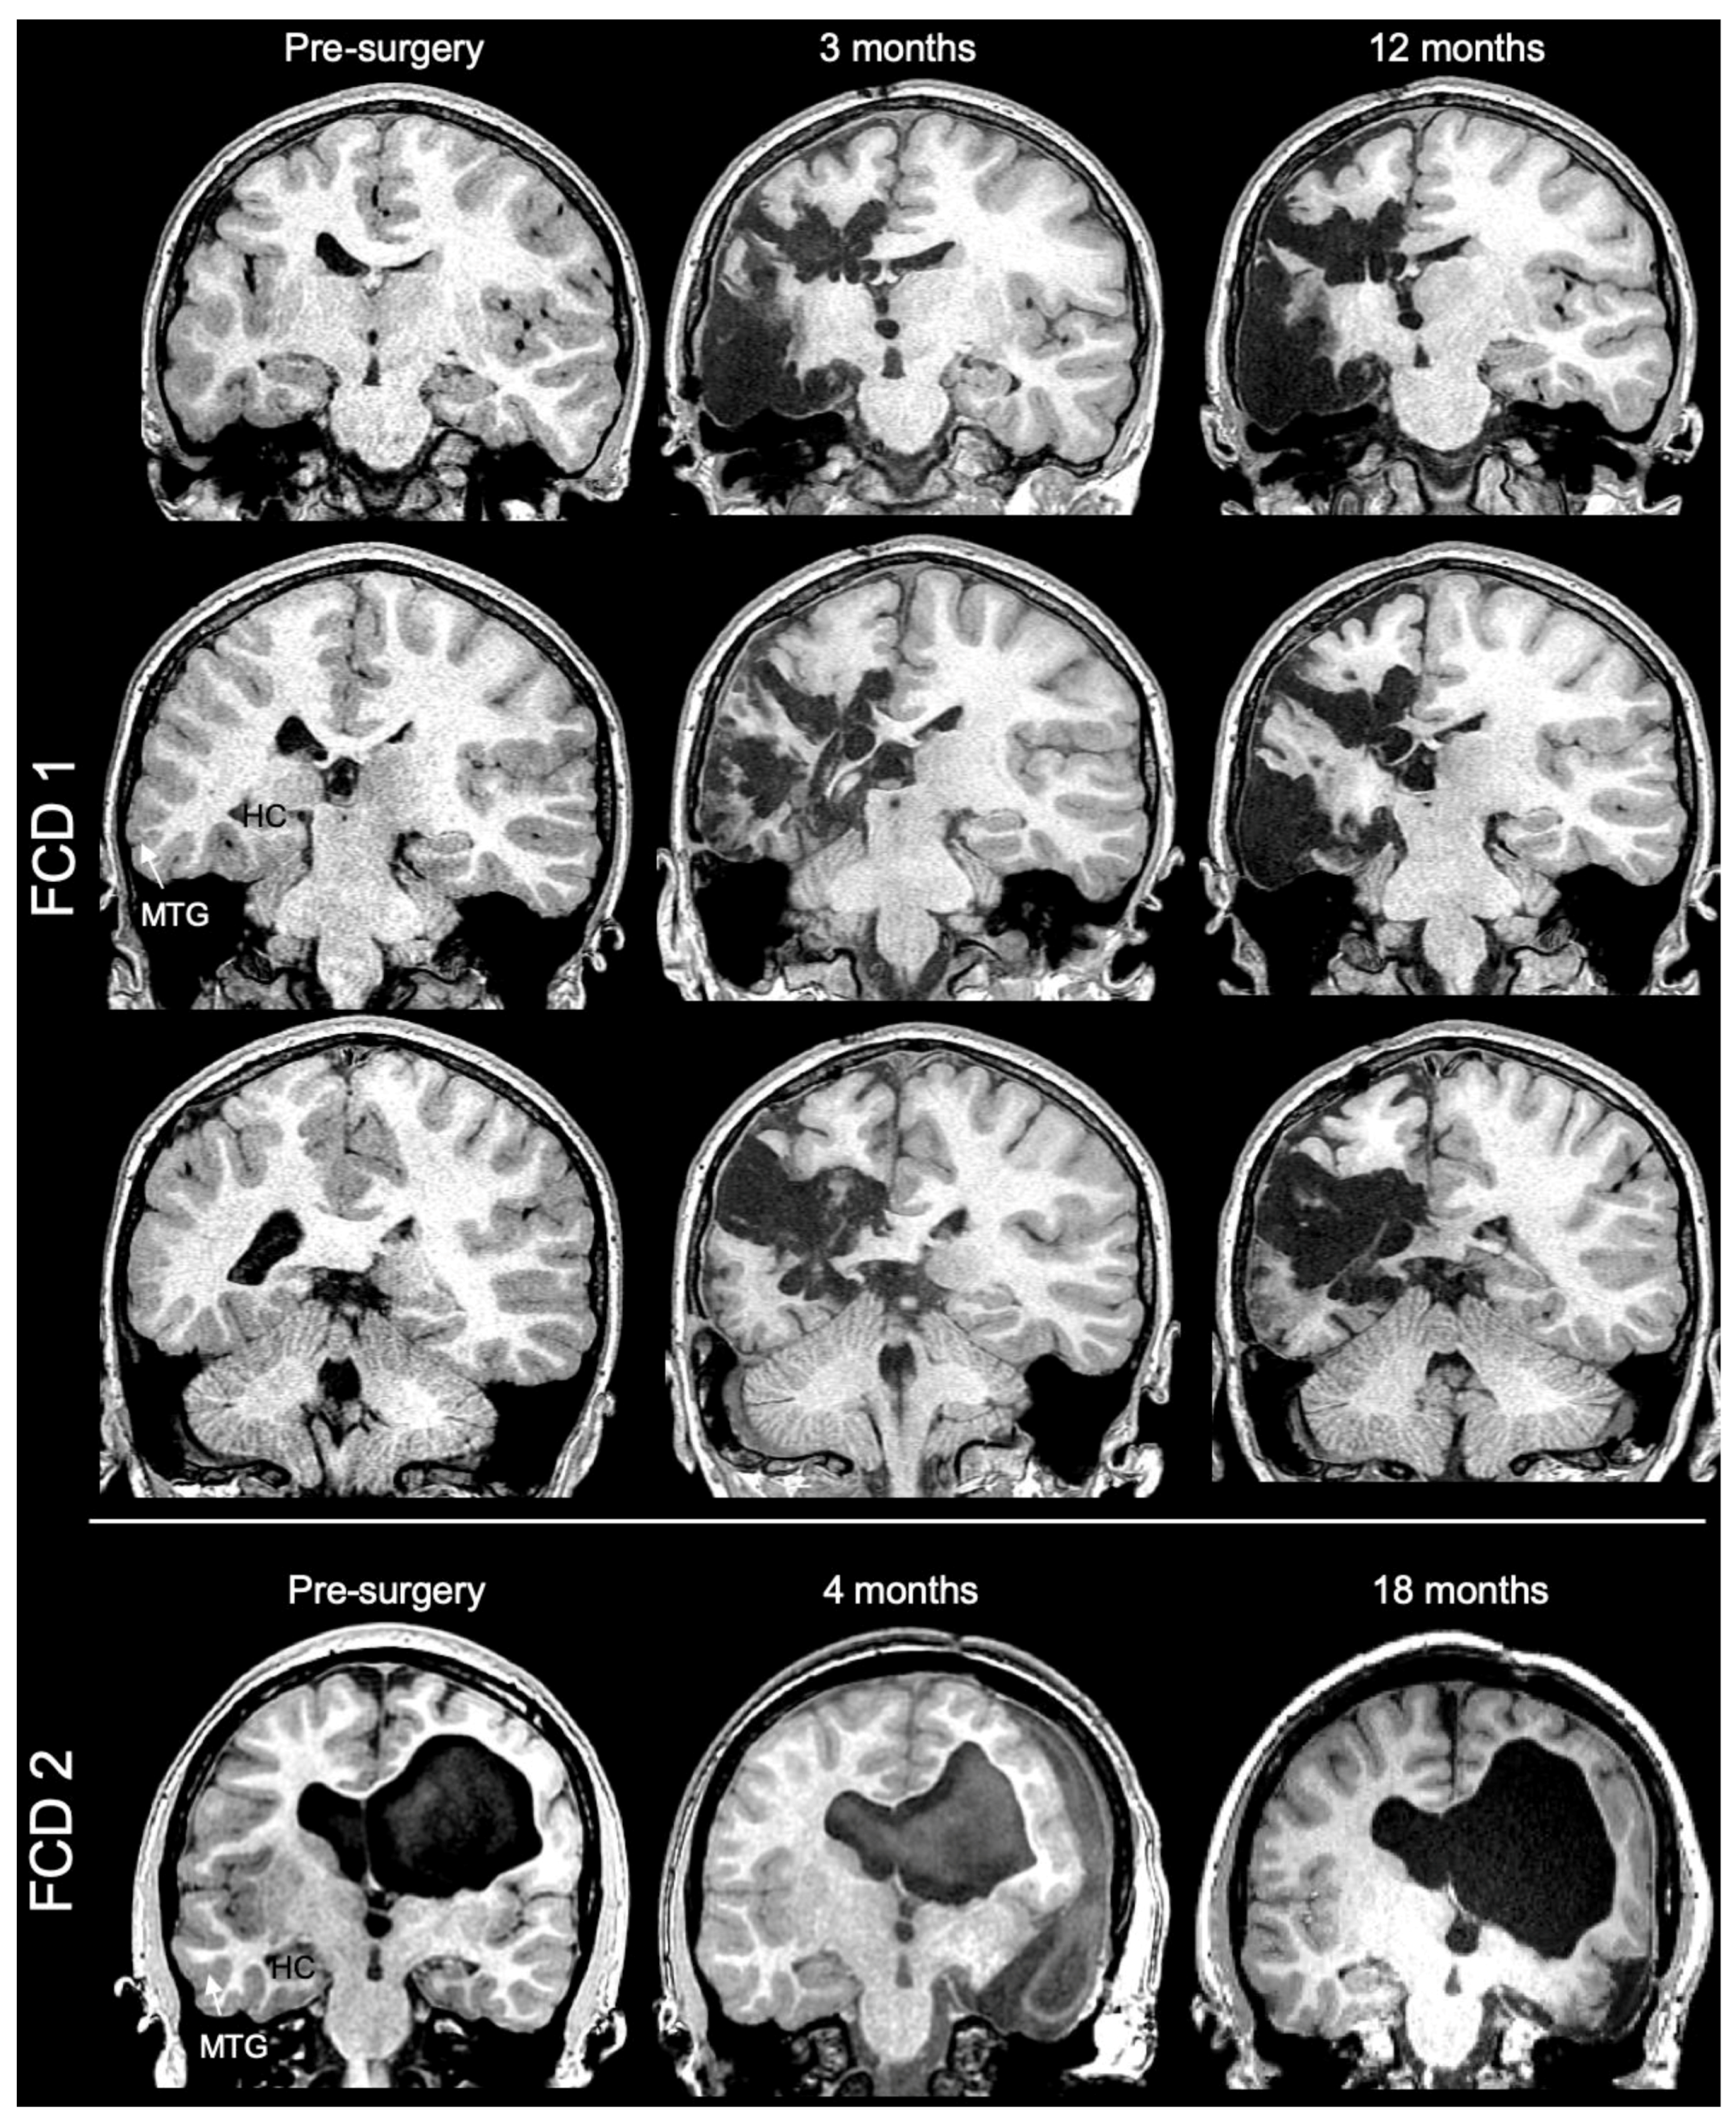

3.1. Magnetic Resonance (MR)-Histology of the Excised Human Cortex

4.1. Ex Vivo MR Imaging as an Analytical Tool in Pediatric Epilepsy